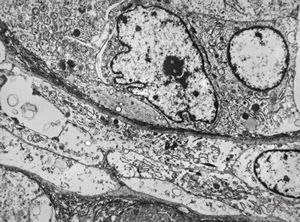

M,2y. | myopathy - regenerating muscle cell